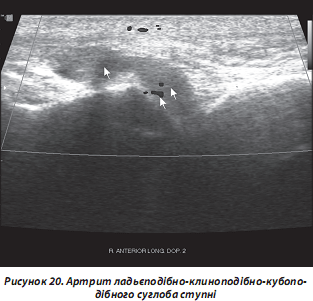

а) випіт у порожнину суглоба (рис. 20);